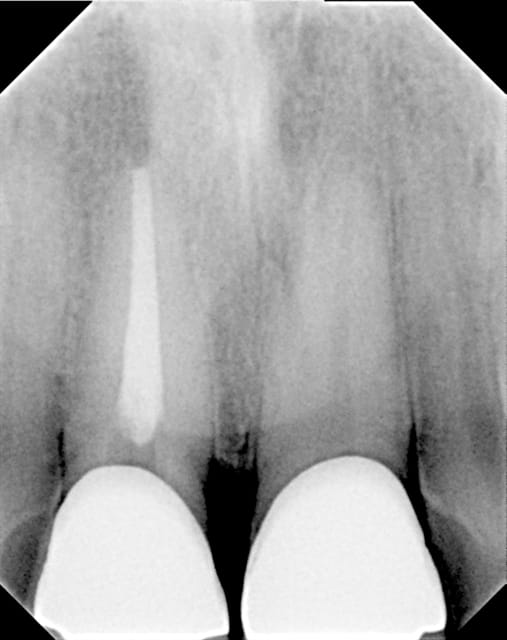

je crois voir un dépassement sur 21,

le dentiste qui a fait ce traitement de canal...sur ma dent...me demande à la fin du traitement (fait sous digue, avec localisateur d'apex, limes motorisées, système calamus pour vertical à chaud), que faite vous quand cela vous arrive?

cela ne m'arrive plus, c'est l'expérience.

sensibilité à la pression quelques semaines sans plus. Présentement sous ortho sans conséquences.

Pr  op d0fenl - Eugenol

Post op tpqpau - Eugenol

Place un implant dès l'ortho terminé, c'est pas jolie cette endo !